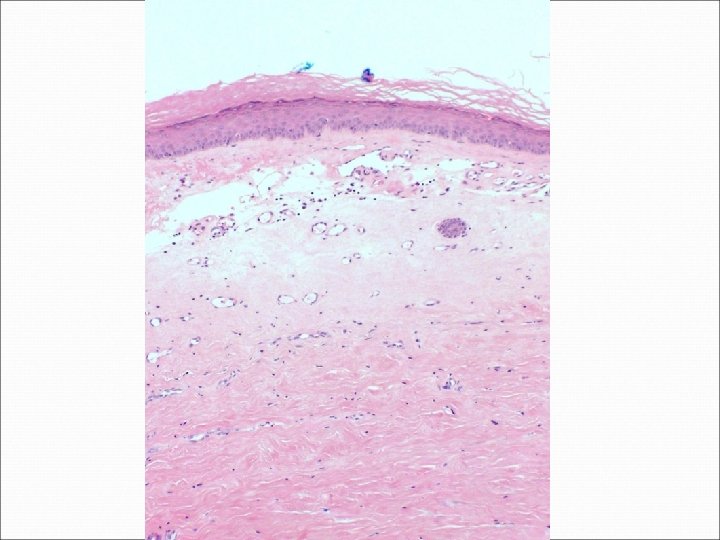

�Case number: 187 �Female 65 yrs. �Extending atrophic white plaque left anterior iliac region.

�Case number: 187 �Female 65 yrs. �Extending atrophic white plaque left anterior iliac region. �Macro: Elliptical piece of skin 20 x 6 x 6 mm.

Most popular diagnosis Morphoea